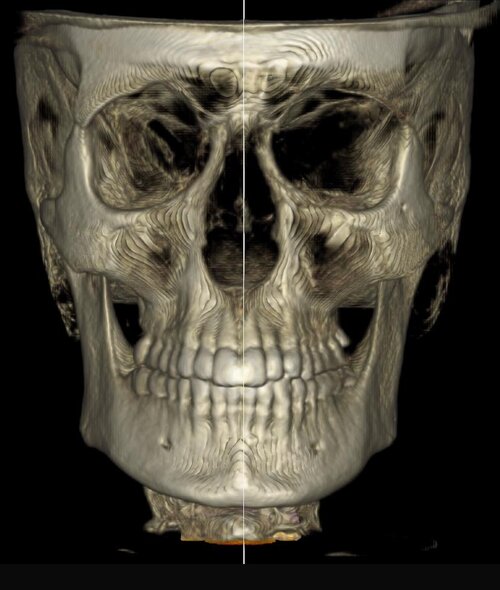

my major failos as you can see from the pics are midface/paranasal deficiency (look how much setback my nasal base is), negative orbital vector (but i suppose a qlf1/2, hlf1, USO would fix this without further procedures), nasolabial folds, malar fullness due to lack of skeletal tissue, flat face etc.

my major failos as you can see from the pics are midface/paranasal deficiency (look how much setback my nasal base is), negative orbital vector (but i suppose a qlf1/2, hlf1, USO would fix this without further procedures), nasolabial folds, malar fullness due to lack of skeletal tissue, flat face etc.